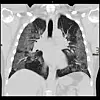

Bildet viser lungene til den 48 år gamle coronapasienten Andre Bergmann Foto: NTB

Bildet viser lungene til den 48 år gamle coronapasienten Andre Bergmann